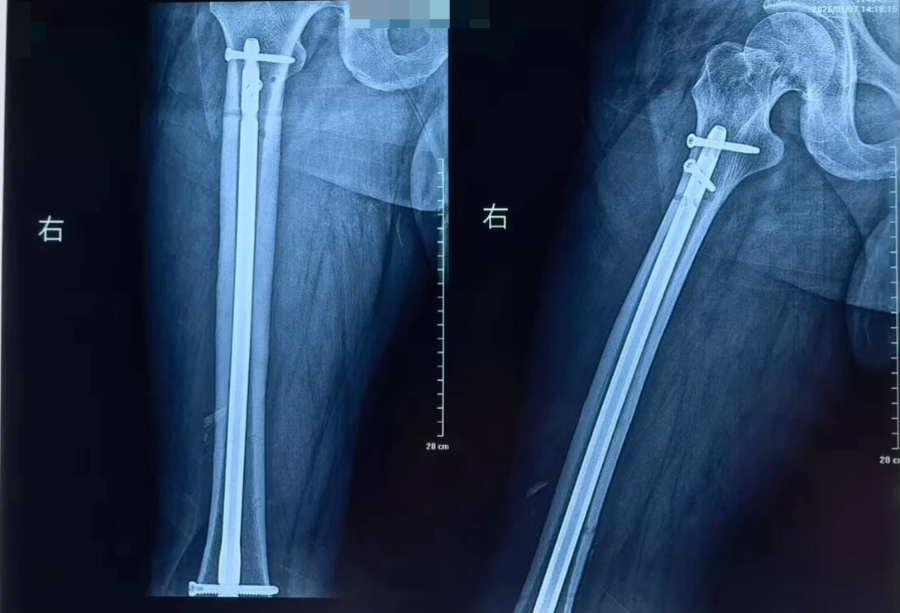

术前

抢救团队凭借丰富的创伤救治经验,在黄金时间内完成伤情评估与抗休克治疗。随后为患者施行骨折复位外固定、髓内钉内固定、解剖钢板内固定等关键手术治疗。手术过程顺利,患者出血得到有效控制,骨折部位获得稳定固定,术后生命体征平稳,安全转入ICU接受进一步监护与支持治疗。